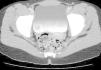

A su llegada a nuestro servicio se realiza analítica general y de marcadores tumorales, sin hallazgos patológicos. Se considera necesaria una ecografía renal y vesical (fig. 1) que muestra una lesión ocupante de espacio, exofítica, en la pared vesical derecha, de unos 4 cm de diámetro. La TC pélvica (fig. 2) confirma una masa parietal intravesical, aunque sin evidencia de afectación ganglionar perivesical ni retroperitoneal.

Figura 2.TC pélvica: masa parietal intravesical, sin evidencia de afectación ganglionar perivesical ni retroperitoneal.